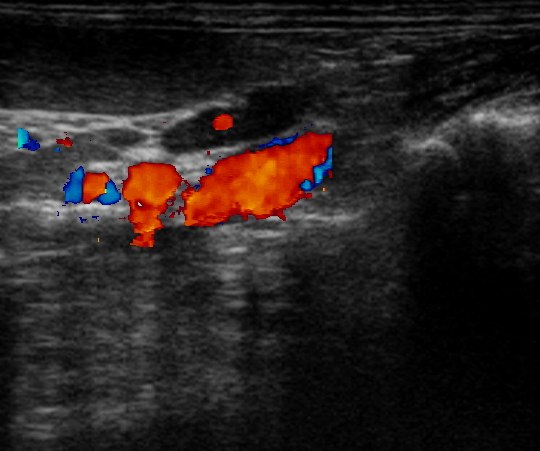

Diagnostiek

Het stellen van een diagnose kan soms net spoorzoeken zijn. Soms is het eenvoudig en soms is het lastig.

Onze diagnostische mogelijkheden hebben we uitgebreid door de aanschaf van vele soorten van apparatuur en het volgen van allerlei cursussen.